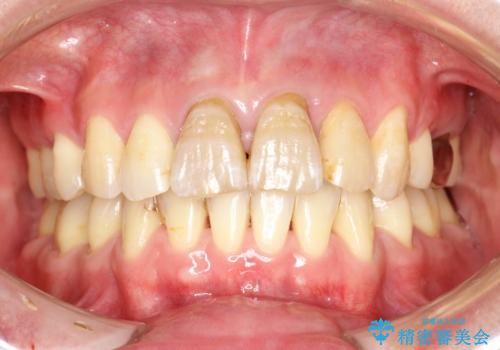

変色した前歯をセラミックできれいに レイヤリングセラミック

前歯のセラミック治療では、他の歯と色調をそろえるのが非常に難しいです。

他の歯に亀裂や白濁など複雑な色合いがある場合、それらをセラミックで再現することも可能ですが、スタンダードのオールセラミックではある程度の同調となります。

かぶせ物の種類: PFZ standard